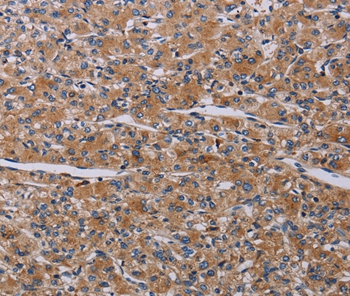

Immunohistochemical analysis of paraffin-embedded Human prostate cancer tissue using #37796 at dilution 1/20.

Immunohistochemical analysis of paraffin-embedded Human ovarian cancer tissue using #37796 at dilution 1/20.